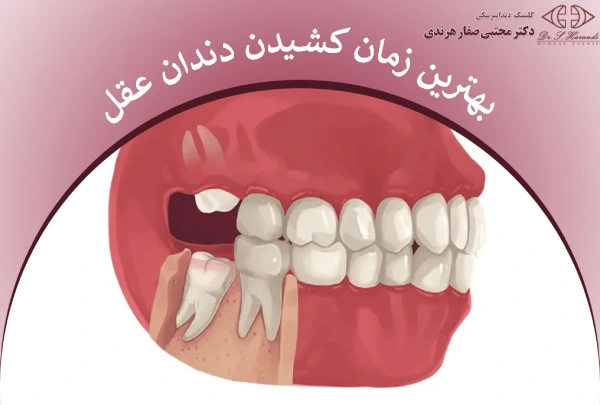

بهترین زمان کشیدن دندان عقل زمانی است که رشد این دندان آخرین در دهان به مرحلهای میرسد که نه تنها درد یا التهاب ایجاد میکند، بلکه میتواند سلامت سایر دندانها را نیز تهدید کند. تشخیص دقیق این زمان بر عهده دندانپزشک متخصص است و هر فرد با توجه به شرایط فک و رشد ریشهها نیازمند ارزیابی جداگانه است. در این مقاله از دکتر صفار هرندی، نکاتی برای انتخاب بهترین زمان کشیدن دندان عقل را با شما به اشتراک میگذاریم.

بهترین زمان کشیدن دندان عقل

بهترین زمان کشیدن دندان عقل زمانی است که باعث درد، التهاب لثه یا فشار به دندانهای اطراف شود. توصیه میشود در اواخر نوجوانی یا اوایل دهه بیست، پیش از بروز عفونت، پوسیدگی یا کیست، دندان عقل بررسی و در صورت نیاز کشیده شود.

گاهی حتی اگر دندان هنوز کامل بیرون نیامده باشد، مشکلاتی مثل تورم لثه یا آسیب به دندانهای مجاور میتواند کشیدن آن را ضروری کند. بهترین کار این است که با بهترین جراح دندان عقل در تهران مشورت کنید تا زمان دقیق و روش مناسب برای شما مشخص شود.

بهترین سن برای کشیدن دندان عقل

معمولاً دندان عقل بین ۱۷ تا ۲۵ سالگی رشد میکند و بیشتر دندانپزشکان توصیه میکنند قبل از ۲۰ سالگی آن را بررسی و در صورت نیاز کشید، زیرا در این سن ریشهها هنوز کامل نشدهاند و جراحی سادهتر و بهبودی سریعتر است.

بعضی افراد ممکن است زودتر، در ۱۴ یا ۱۵ سالگی، به کشیدن دندان عقل نیاز پیدا کنند و برخی دیگر تا حدود ۲۵ سالگی میتوانند صبر کنند. هر چه سن بالاتر برود، ریشهها کاملتر شده و جراحی پیچیدهتر و بهبود کمی کندتر میشود.

به طور کلی، بهترین زمان کشیدن دندان عقل بستگی به رشد و جایگاه دندان در فک هر فرد دارد و نمیتوان یک زمان ثابت برای همه تعیین کرد. معمولاً بررسی و کشیدن دندان عقل در سنین ۱۸ تا ۲۴ سالگی توصیه میشود، زیرا در این سن ریشهها هنوز کامل نشده و جراحی سادهتر و بهبود سریعتر است. با این حال، در مواردی که دندان عقل سالم، کامل روییده و فضا کافی دارد، ممکن است نیازی به کشیدن آن نباشد. تصمیم نهایی باید با مشاوره تخصصی دندانپزشک گرفته شود.